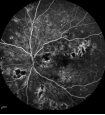

3.png

正常眼底造影

4.png

早期糖网-血管瘤样改变